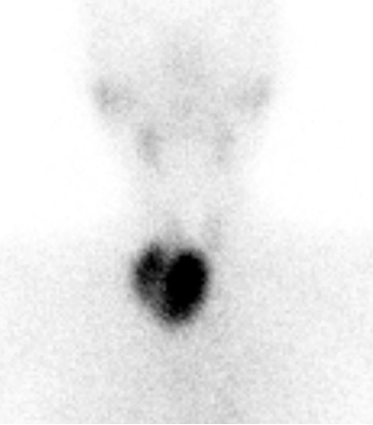

心肌灌注显像:

心血管功能好不好?

心肌灌注显像是诊断冠心病患者心肌缺血准确且循证医学证据最充分的无创性方法,可以准确判断冠状动脉狭窄时有无心肌缺血、评估缺血范围、评估是否需行支架置入以及评估支架置入后疗效,在心肌炎、心肌病、微血管障碍等心血管疾病中也有应用。

案例:心绞痛患者完善负荷+静息心肌灌注显像提示左室前壁、间壁局部心肌缺血,为临床选择治疗方案提供依据。